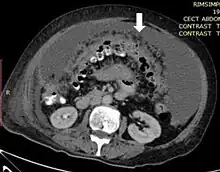

| Axial abdominal computed tomography featuring omental caking due to peritoneal carcinomatosis | |

Omental cake is a radiologic sign indicative of an abnormally thickened greater omentum.[1] It refers to infiltration of the normal omental structure by other types of soft-tissue or chronic inflammation resulting in a thickened, or cake-like appearance.[2]

Due to the variety of symptoms experienced by patients with omental caking,[5] omental cakes are most frequently discovered on abdominal computed tomography (CT) or ultrasound. Plain film radiography (X-ray) is not a suggested modality for investigating the spread of cancerous cells in the abdomen due to the poor spatial resolution amongst soft-tissue densities. Contrast resolution obtained through CT allows radiologists to investigate omental caking for morphology, intraperitoneal fluid, and regional lymphadenopathy assists in proper diagnosis so clinicians, surgeons, and oncologists can plan the appropriate course of treatment.[8]